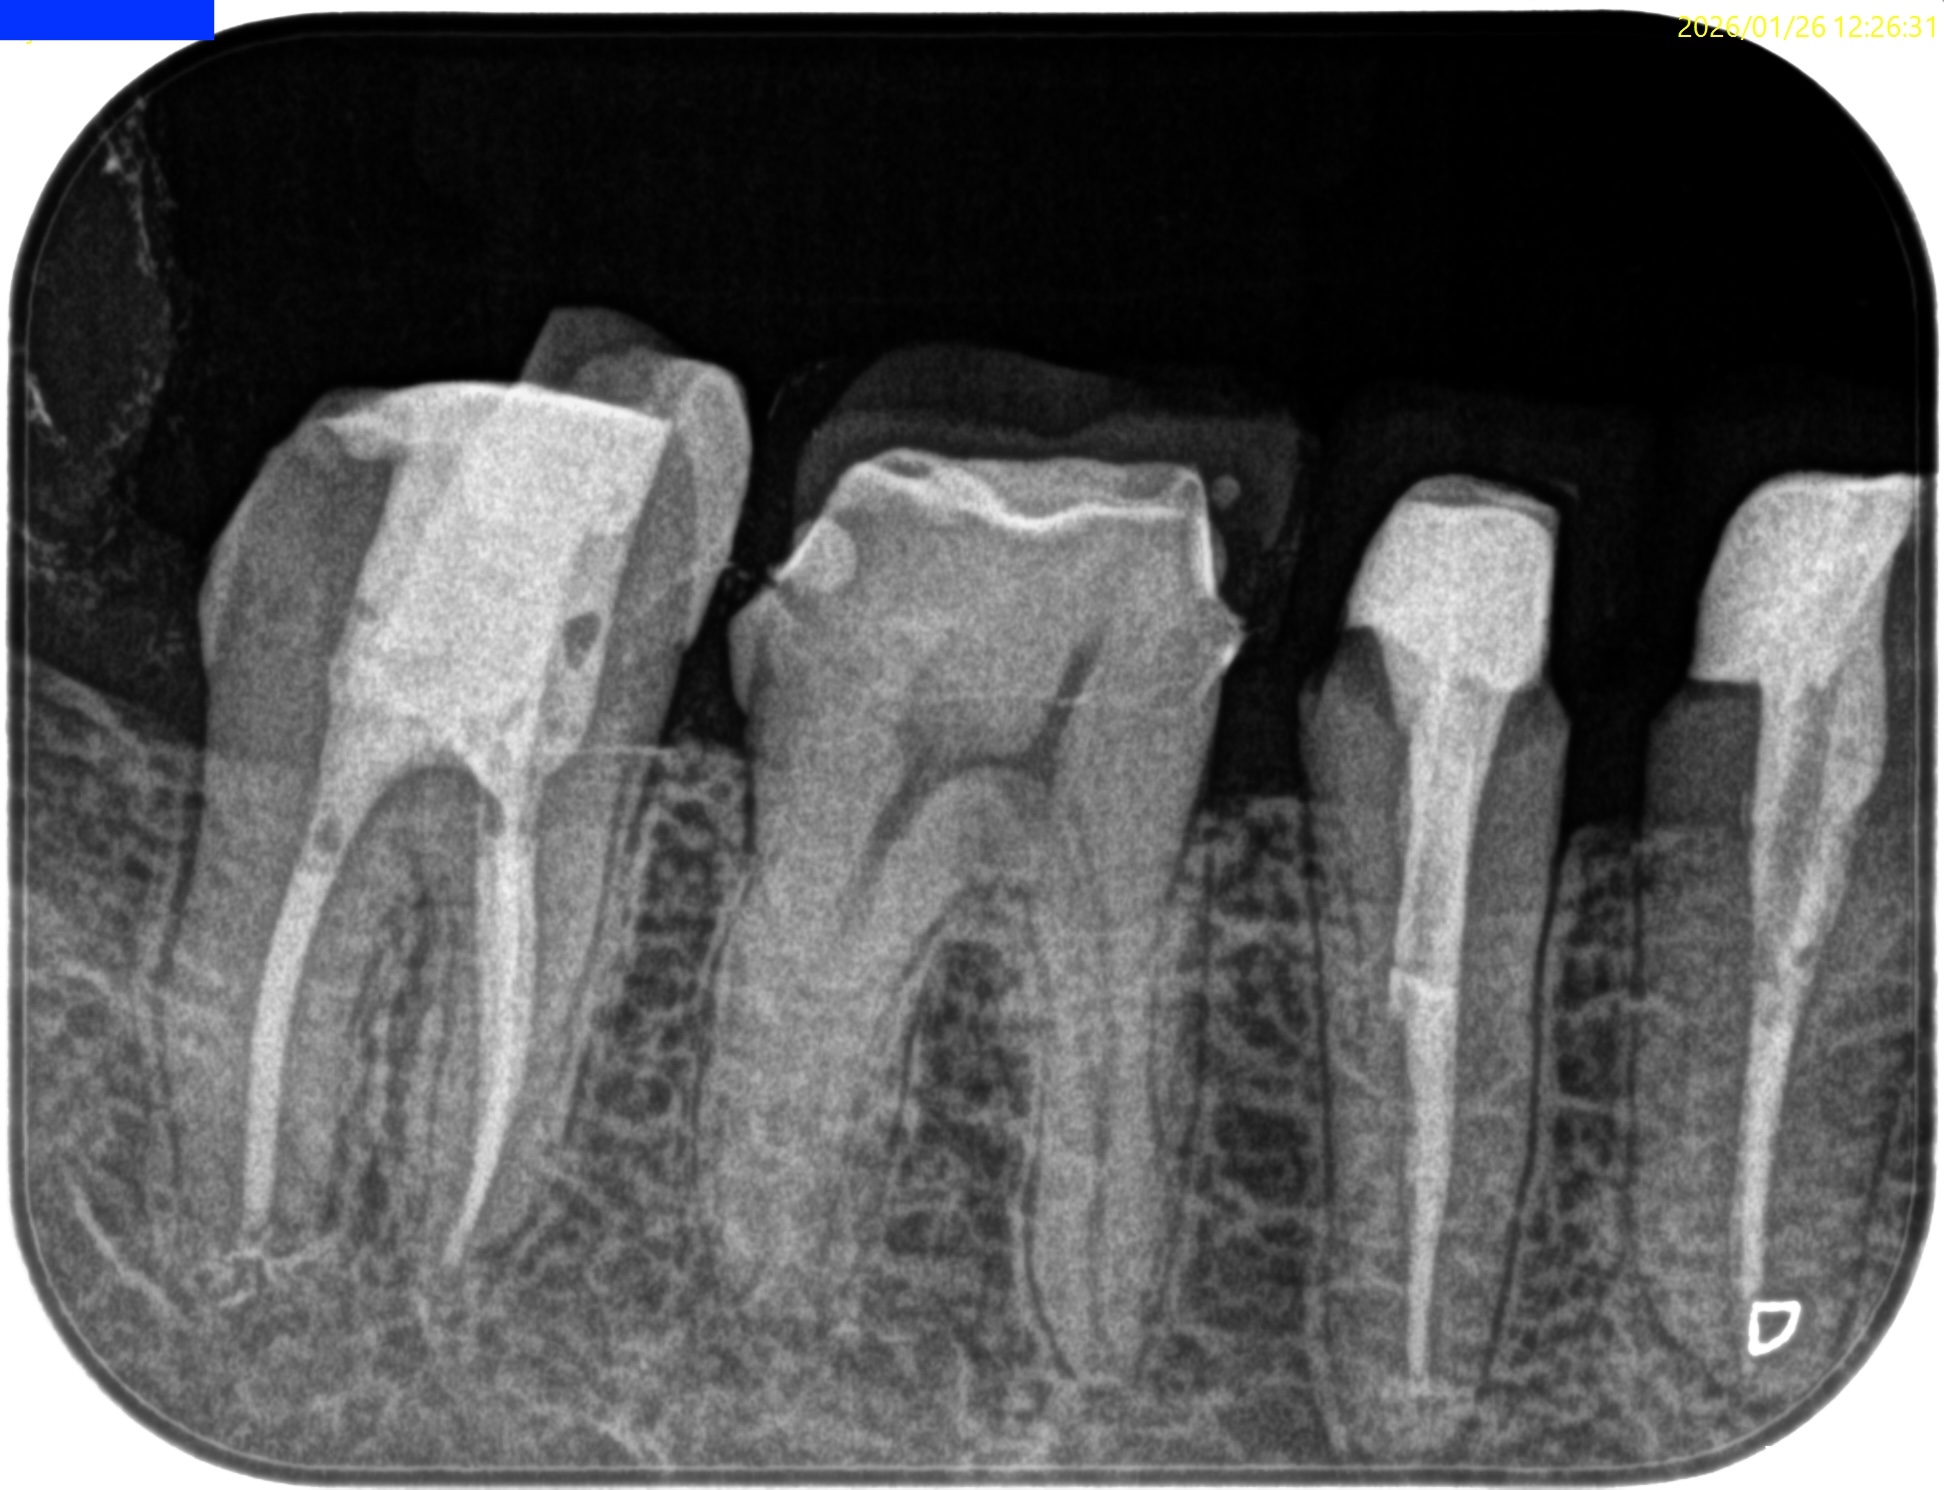

Pre-op Endo test(2026.1.26)

#31 Cold++1/15, Perc.(+), Palp.(-), BT(-), Perio Probe(WNL), Mobility(WNL)

遠心根に直接覆髄的な治療で痛みが出ている。

そして根尖部にはかなり小さいが病変的なものが見える。

根尖病変のない近心根は

96%

Sjorgren 1990 Factors affecting the long-term results of endodontic treatment

若干小さな病変のようなものがある遠心根は

86%

de Chevigny 2008 Treatment outcome in endodontics: the Toronto study–phase 4: initial treatment